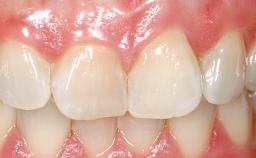

A 30-year-old female patient was referred to the office for the treatment of tooth 11. Her chief concern at the initial visit was to inquire, “Why is my tooth pink?” Upon clinical examination, it was determined that tooth 11 had a previous history of trauma and that the clinical crown had become noticeably pink in color as a result of internal resorption. This diagnosis was confirmed radiographically, indicating a large radiolucency involving the central and distal portions of the clinical crown. It was determined that restoration of this tooth was not possible, and that extraction was indicated. The presence of a mid-line diastema, which the patient wanted to reproduce, directed the treatment plan for tooth replacement utilizing a dental implant.